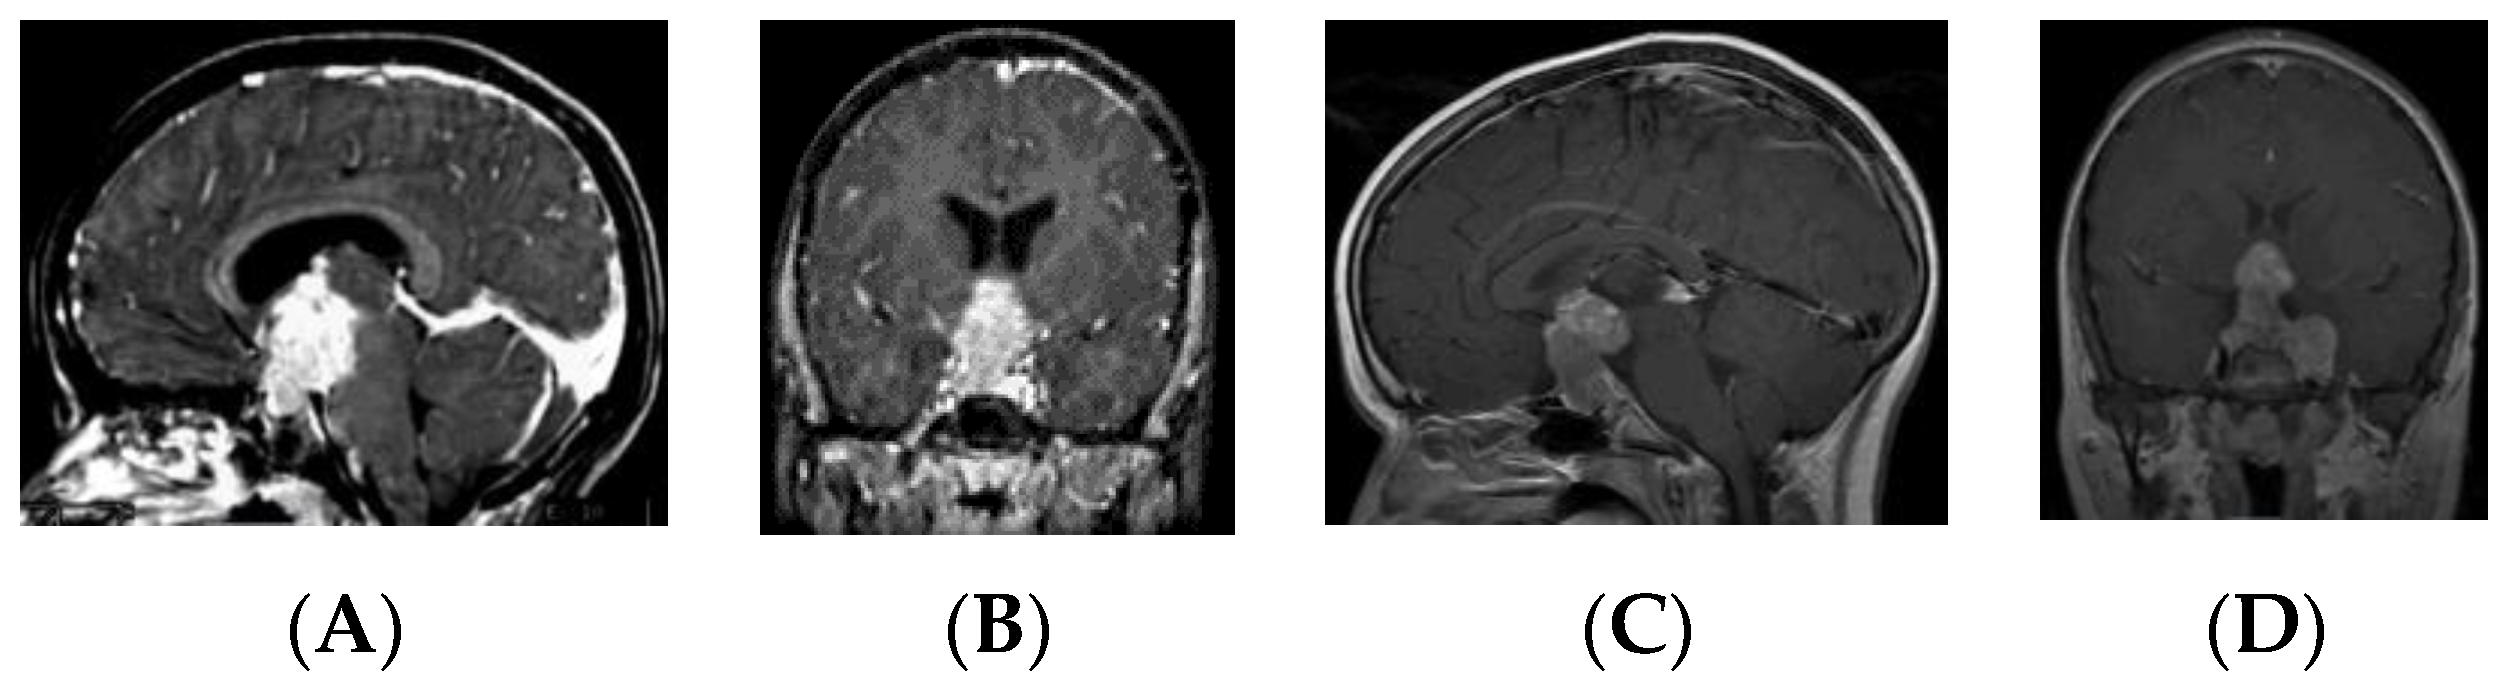

• Type II: Globular anterior III ventricle mass extending to the sella turcica (Figure 3);

• Type III: Globular mass extending from the floor of III ventricle to sella turcica (Figure 4);

Figure 3. Type II. Post-contrast MR, sagittal (A) and coronal (B) views of a patient with S-GCT. Note the third ventricle tumor extension into the sella turcica. Post-contrast MR, sagittal (C) and coronal (D) views of a patient with S-GCT demonstrate further lateral extension to the cavernous sinus.

Patients in the S-GCT group skewed toward masses of the anterior III ventricle. Of 22 S-GCTs: seven were Type Ia or Ib (Figure 1 and Figure 2), seven were Type II (Figure 3), and six were Type III (Figure 4). These 20 S-GCTs were all globular appearance. In four patients (two each of S-GCT Type II and III), the tumor extended laterally into the cavernous sinus (Figure 3C,D; Figure 4C,D). Each of these patients presented with cranial nerve dysfunction. The two non-globular S-GCTs were small and confined to the PS (Types IV and V).